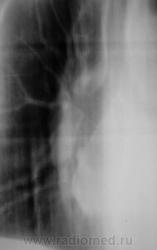

1 срез.

2 срез.

Хорошие томограмы, жаль нет бочка посмотреть вентиляцию нижней доли, а так конечно в просвете бронха дополнительная тень, предсердие бы оттеснило весь бронх. Надо рекомендовать бронхоскопию.